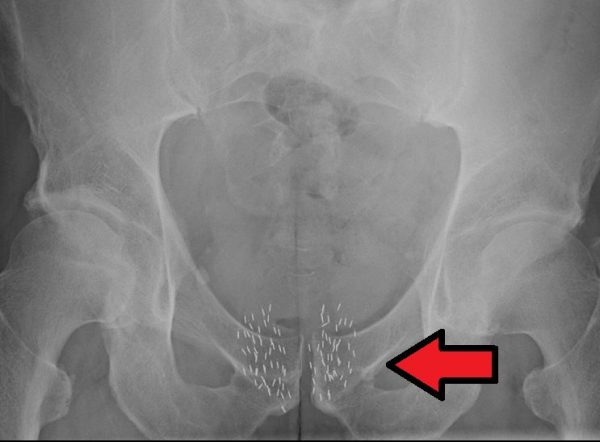

The therapy also known as brachytherapy involves using the radiation sources close to the area of the body containing the tumor. In some cases, the doctors insert the radiation directly into the tumor. The treatment is also known as seed implantation. It delivers high doses of radiation directly into the cancerous site. But, it spares the healthy tissue surrounding the malignant cells. With brachytherapy, your oncologist inserts or implant radioactive materials at the specific site of your cancer. Depending on the type of cancer, the placement may remain in your body temporarily or permanently. The radioactive materials are called seeds. These seeds release the radiation into the tumor over a period (a few months). The radiation seeds decay within a year. It remains on the specific site safe for the rest of your life.

To start the procedure, your doctor uses a stretchy tube called a catheter. It aids the doctor place the radioactive seeds into the tumor. In some cases, brachytherapy is placed into the tumor using a larger device known as an applicator. How the doctor places the radioactive seeds depends on the type of cancer you suffer. Before beginning the treatment, the doctor places the applicator into the body. After placing the catheter or applicator in the specific site, your doctor places the radiation source inside it. Depending on cancer, your doctor places the radiation source for minutes, days or lifelong. The type of radiation source, cancer you suffer, the specific site affected by cancer, etc. aids in deciding the duration of placing the radiation.

Depending on the type of brachytherapy, the treatment duration varies. For a low-dose rate therapy, the radiation seeds stay in the cancer site for one to seven days. You need to stay in the hospital for the duration. Before leaving the hospital, your doctor removes the catheter or applicator. For High dose brachytherapy, the session lasts for ten to twenty minutes. Your doctor repeats the session a couple of times in a day for two to five days. In some cases, you need to undergo the session once a week for at least two to five weeks. Only after the sessions, the doctor removes the applicator or catheter. The permanent implants are placed on the cancer sites and left for the rest of your life. The catheter is removed after placing the seeds.